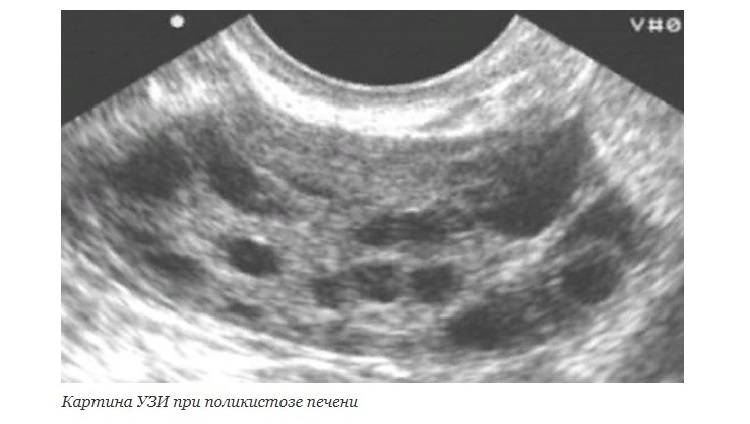

- УЗИ, или ультразвуковое исследование органов брюшной полости;

Базовые методы диагностики поликистоза с поражением печени – это УЗИ и КТ.

На ФГДС (фиброгастродуоденоскопии) никаких значимых изменений, позволяющих пояснить симптоматику, не было. Однако УЗИ брюшной полости выявило наличие кистозных образований в печени. Ни одно из них не оказалось настолько крупным, чтобы речь шла о немедленном хирургическом вмешательстве. Однако пациентке было рекомендовано наблюдение, назначены симптоматические препараты для облегчения тошноты и изжоги.